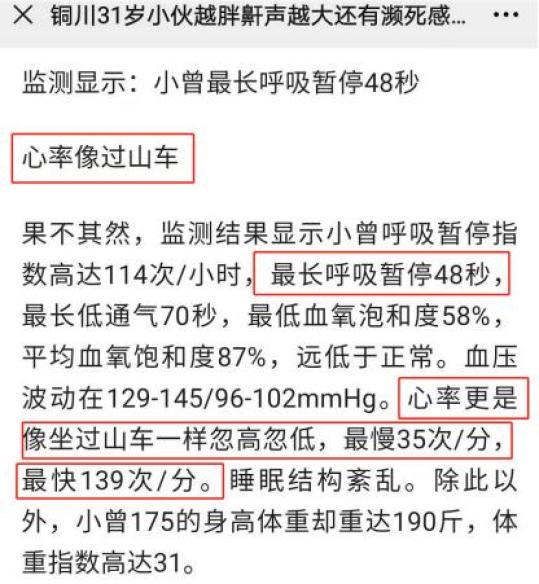

31岁的曾先生,身高175,体重190斤。最近半个月睡觉时总会被憋醒,大汗淋漓、胸闷气喘。

31岁的曾先生,身高175,体重190斤。最近半个月睡觉时总会被憋醒,大汗淋漓、胸闷气喘。他来到医院一检查,严重睡眠呼吸暂停综合征。

据流行病学调查显示,“睡眠呼吸暂停综合症”在一般人群中患病率为17%,在肥胖人群中患病率高达40%~70%。